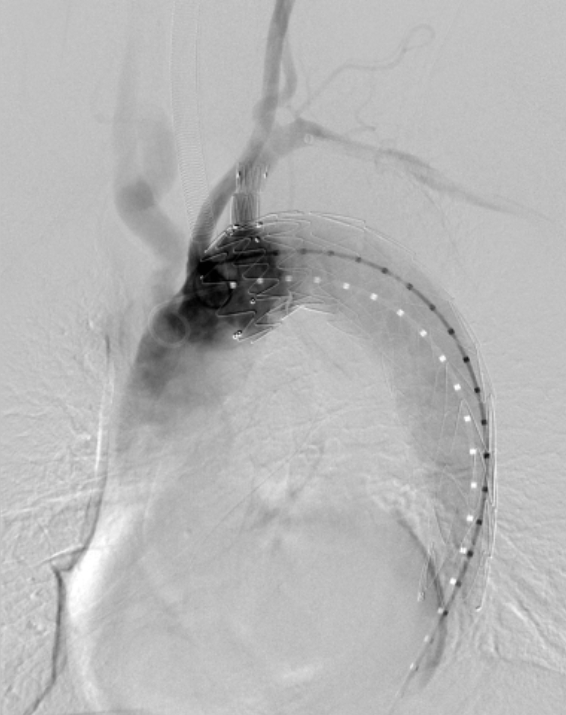

▲ 术后造影

该最后一例入组患者经术前评估诊断为Stanford B型胸主动脉夹层,近端累及左锁骨下动脉(LSA),需进行胸主动脉腔内修复术(TEVAR)。对于常规直管型支架而言,患者健康锚定区不足,存在支架移位及内漏的潜在风险。综合考虑之下,戴向晨教授及其团队决定使用新一代Cratos®分支型支架进行手术,其主体支架可向近端拓展获得充足的锚定区,且一体化分支支架可同时重建LSA。整个手术过程流畅顺利,术后造影显示,Cratos®分支型支架定位精准,无移位;经主动调节支架近端后,支架“鸟嘴”现象得到显著改善;病变部位得到有效隔绝,未发生内漏;弓上分支血管血流通畅,手术圆满成功。